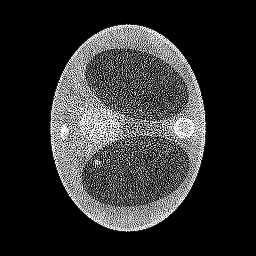

We assume to measure a total of photons and compute synthetic data from eq. 11 for a phantom electron density modeling a transversal slice of a human thorax. The phantom (see fig. 2(b)) consists of characteristic functions of ellipses of different sizes and opacities and is a modified version of an earlier phantom which was used in [12]. It is 28.4 cm resp. 21.3 cm wide at its largest and smallest diameters and its gray values are chosen as electron densities of materials typical in a human thorax [15, 3, 30].

In the reconstruction, a suitable choice for the regularization parameter is computed by the L-curve method. In fig. 3(e) we see that a reconstruction of the electron density from works well and the TV penalty term reduces the effects from the Poisson noise sufficiently. However, adding the component (fig. 3(f)) to the spectrum distorts the reconstruction. Due to the enormous noise level brought into the model by the component , the TV-regularized solution suffers from bad quality. Details are less visible or harder to localize and intensities of the different regions are altered complicating material recognition.

The method is tested for two synthetic phantoms; firstly, the thorax phantom already used in section 2. Figure 8 shows how the algorithm succeeds in decreasing the impact of the higher-order scattering. The ground truth is displayed in fig. 8(a). Expectably, the CT reconstruction (fig. 8(d)) is not accurate enough, but can be used as a prior to estimate the nonlinear weight function . Using , the CST reconstruction is computed. For comparison, we give both the solution of eq. 25 (without ) and eq. 26 (with ). As in section 2, eq. 25 cannot yield a useful reconstruction. The minimizer when is the Kullback-Leibler divergence (13) and is very noisy (fig. 8(b)) and using TV regularization, some noise can be filtered out, but only at the cost of losing small details of lower contrast (fig. 8(e)). As desired, applying to the data reduces the noise level, see fig. 8(c) and fig. 8(f) (with TV regularization). After applying , we use the norm as data fidelity measure. Densities and contrasts are accurately recovered and previously vanished details can be correctly located.